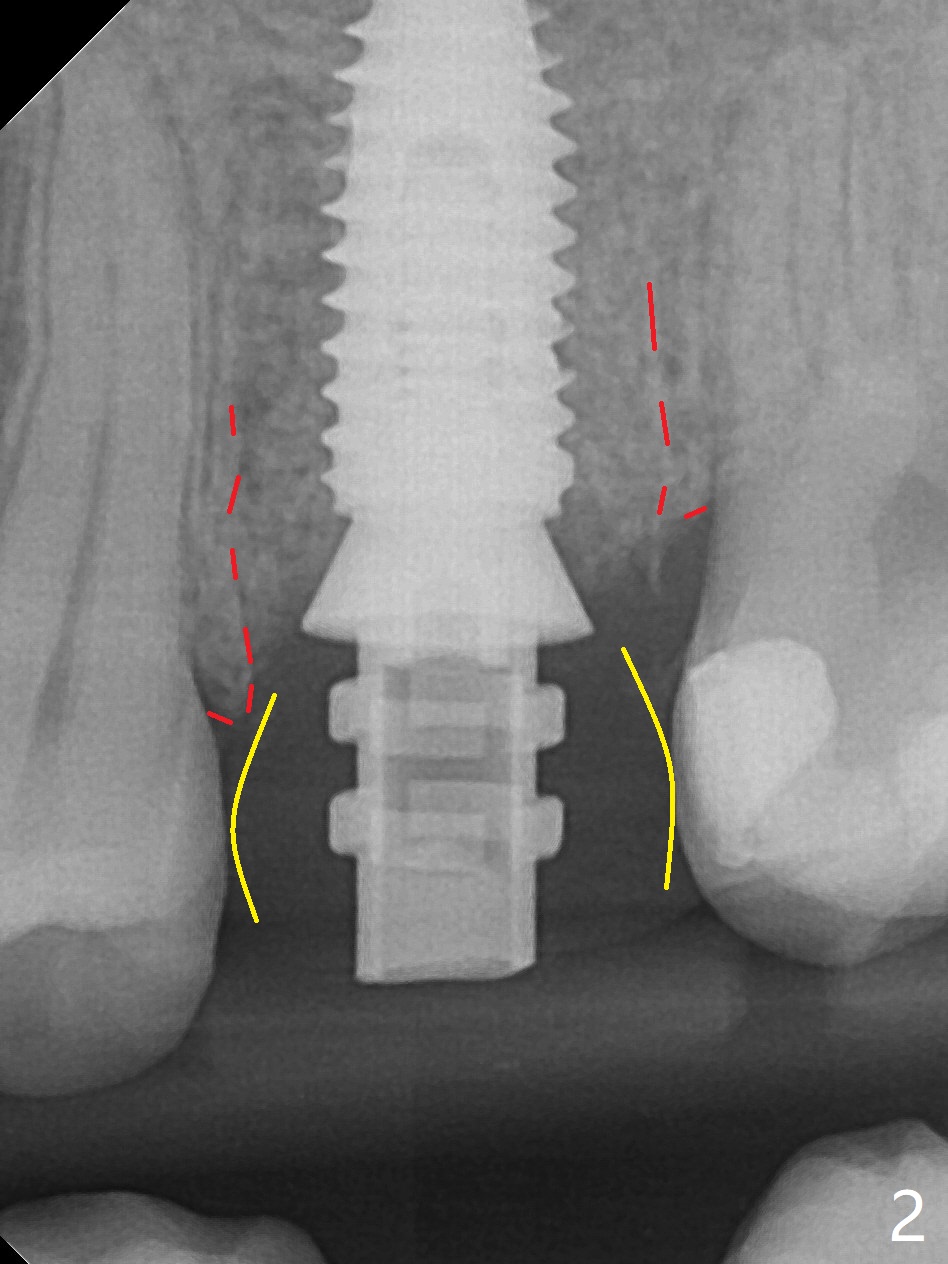

When a 4.5x10 mm implant is placed with sinus lift at #14 (Fig.1), a 5.2x8(2) mm temporary abutment is inserted with height adjustment. Advantage is that an immediate provisional (Fig.2 yellow lines; Fig.3 P) has an ideal emergency profile so that there is less chance of food impaction associated with the future permanent crown. It appears that the mesial portion of bone graft in the mesial gap has been converted to the native bone (lamellar) in 3 months (Fig.4). Bone graft appears to be integrated to the native bone and the implant 14 months postop (Fig.5).